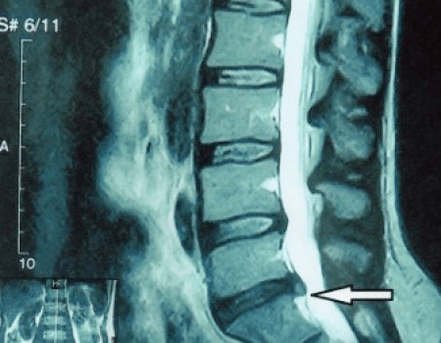

Because the disc itself can only be seen with CT or MRI, magnetic resonance and X-ray computed tomography are used to elucidate the internal structure of the cartilage as well as structures such as protrusions and hernias.Therefore, the diagnosis can be made accurately with the help of these methods, and the tomographic results can be used as an indication or even a local guide for neurosurgical hernia surgical treatment.

- If you have a hernia, then you need to monitor it dynamically, undergo regular MRI examinations, avoid increasing its size, or undergo modern minimally invasive surgical treatment, because without exception, all conservative methods of treating the exacerbation of osteochondrosis leave the hernia in place and only eliminate temporary symptoms: inflammation, pain, shooting and muscle spasms.

It is recommended that every patient undergo an MRI after symptom progression, when complications arise, and consult a neurosurgeon.Modern minimally invasive surgeries can safely remove sizable hernias without lengthy hospital stays, without being forced to lie down for days, and without affecting quality of life because they are performed using modern videoendoscopy, radiofrequency, laser technology or cold plasma.You can vaporize some of the kernels and reduce the pressure, thereby reducing the risk of hernias.And you can essentially eliminate the defect, that is, get rid of it completely.

There is no need to be afraid of hernia surgeries; these are no longer the open surgeries of the 1980s and 1990s with their dissection of muscle, blood loss, and subsequent lengthy recovery period.They're more like doing a small puncture under X-ray control and then using modern technology.